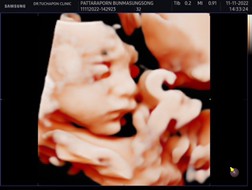

บ้านนี้เพิ่งไปซาว 4 มิติมาตอนอายุครรภ์ 28week ค่ะ

27 วีค ค่ะ